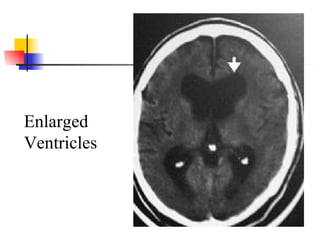

Diagnostic studies Ventricle enlargement on CT or MRI Severity graded by ratio of maximal frontal horn width divided by transverse inner diameter of skull 0.32 minimal for NPH but 0.40 more typical Lack of hippocampus or cortical atrophy Periventricular and cortical white matter lesions may be found in patients with NPH Large number white matter lesions may be marker for poor response to shunting

Enlarged Ventricles